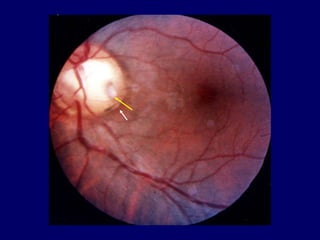

Defect in the juxta-papillary choroid (white arrow); Pit, yellow arrow

Notice the atypical coloboma

Defect in the juxta-papillary choroid ,(white arrow ); Pit, (yellow arrow)

Defect in thejuxta-papillary choroid (white arrow); Pit, yellow arrow

Defect in thejuxta-papillary choroid ,(white arrow ); Pit, (yellow arrow)